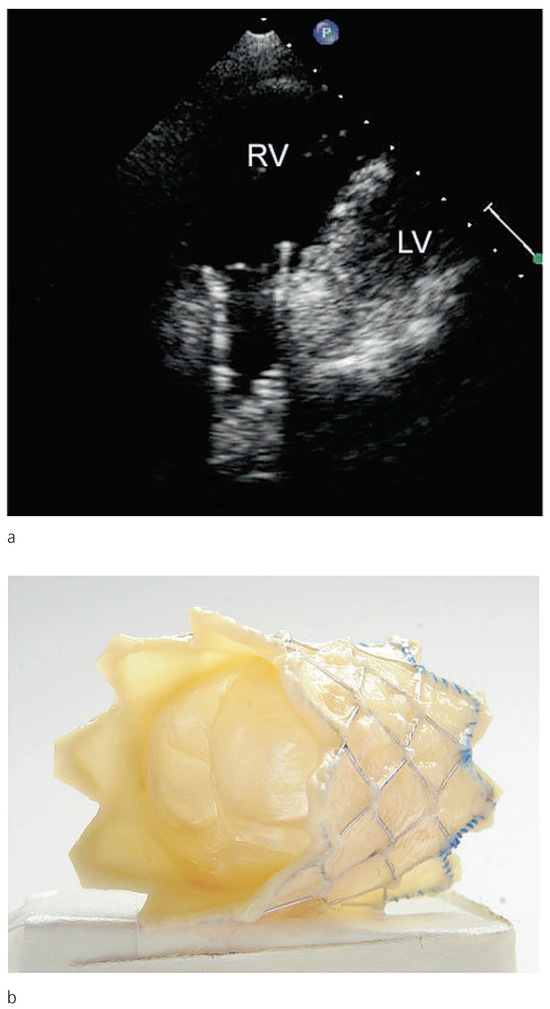

Interesting Images

My Heart Dances

by Marcus Mutschelknauss, Hans Rickli and Peter Ammann

Cardiovasc. Med. 2009, 12(9), 251; https://doi.org/10.4414/cvm.2009.01442 - 18 Sep 2009

Cited by 1 | Viewed by 106

Abstract

Case presentation

A 33-year old woman was admitted for persistent palpitations over the past six years [...] Full article

Show Figures

Figure 1